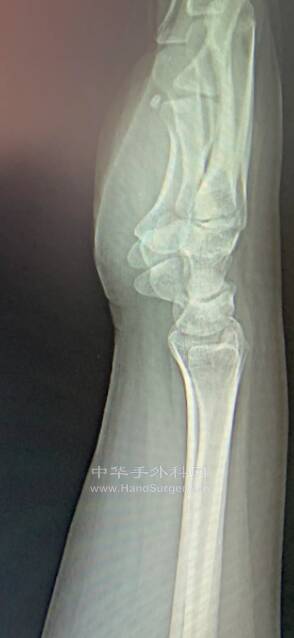

微信截图_20220520233236.png

这个侧位片是如何拍照的?前臂处于何种旋转位置?

上图的侧位片拍摄时

答案是:前臂旋后位拍的

因为此片子上的尺骨茎突在背侧